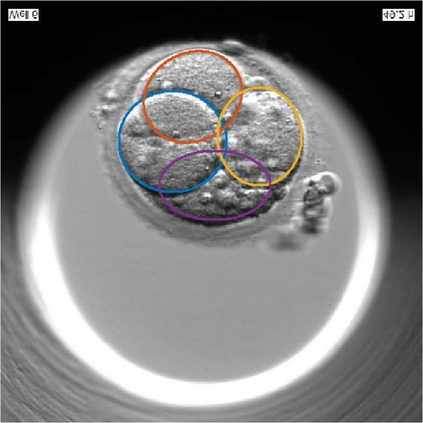

We present a novel method for identification of the boundary of embryonic cells (blastomeres) in Hoffman Modulation Contrast (HMC) microscopic images that are taken between day one to day three. Identification of boundaries of blastomeres is a challenging task, especially in the cases containing four or more cells. This is because these cells are bundled up tightly inside an embryo's membrane and any 2D image projection of such 3D embryo includes cell overlaps, occlusions, and projection ambiguities. Moreover, human embryos include fragmentation, which does not conform to any specific patterns or shape. Here we developed a model-based iterative approach, in which blastomeres are modeled as ellipses that conform to the local image features, such as edges and normals. In an iterative process, each image feature contributes only to one candidate and is removed upon being associated to a model candidate. We have tested the proposed algorithm on an image dataset comprising of 468 human embryos obtained from different sources. An overall Precision, Sensitivity and Overall Quality (OQ) of 92%, 88% and 83% are achieved.